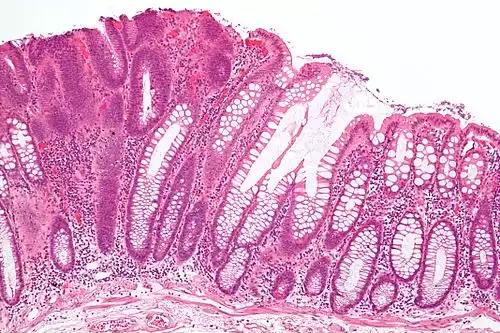

آدنوم. آدنوم یا آدنوما ( به انگلیسی: Adenoma ) به تومور خوش خیم با منشأ بافت غددی گفته می شود. این تومور در غددی مانند هیپوفیز، کولون، کبد، تیروئید، پاراتیروئید، غده فوق کلیوی و… تشکیل می شود. علائم آن اغلب ناشی از فشار بر بافتهای مجاور و ترشح هورمونهای مربوط به بافت منشأ می باشد. مثلاً آدنوم هیپوفیز با فشار بر بافتهای مجاور موجب تاری دید و سردرد شده و با ترشح هورمون رشد منجر به درشت پایانکی ( آکرومگالی ) می شود.

آدنوما اصولاً خوش خیم است ولی ممکن است بافت تومورال بدخیم نیز باشد. به تومور بدخیم با منشأ بافت غددی آدنوکارسینوم می گویند. گاه توده های آدنومی بعد از چند سال به کارسینوم مبدل می شوند مانند سرطان روده بزرگ.

آدنوما اصولاً خوش‌خیم است ولی ممکن است بافت تومورال بدخیم نیز باشد. به تومور بدخیم با منشأ بافت غددی آدنوکارسینوم می‌گویند. گاه توده‌های آدنومی بعد از چند سال به کارسینوم مبدل می‌شوند مانند سرطان روده بزرگ.